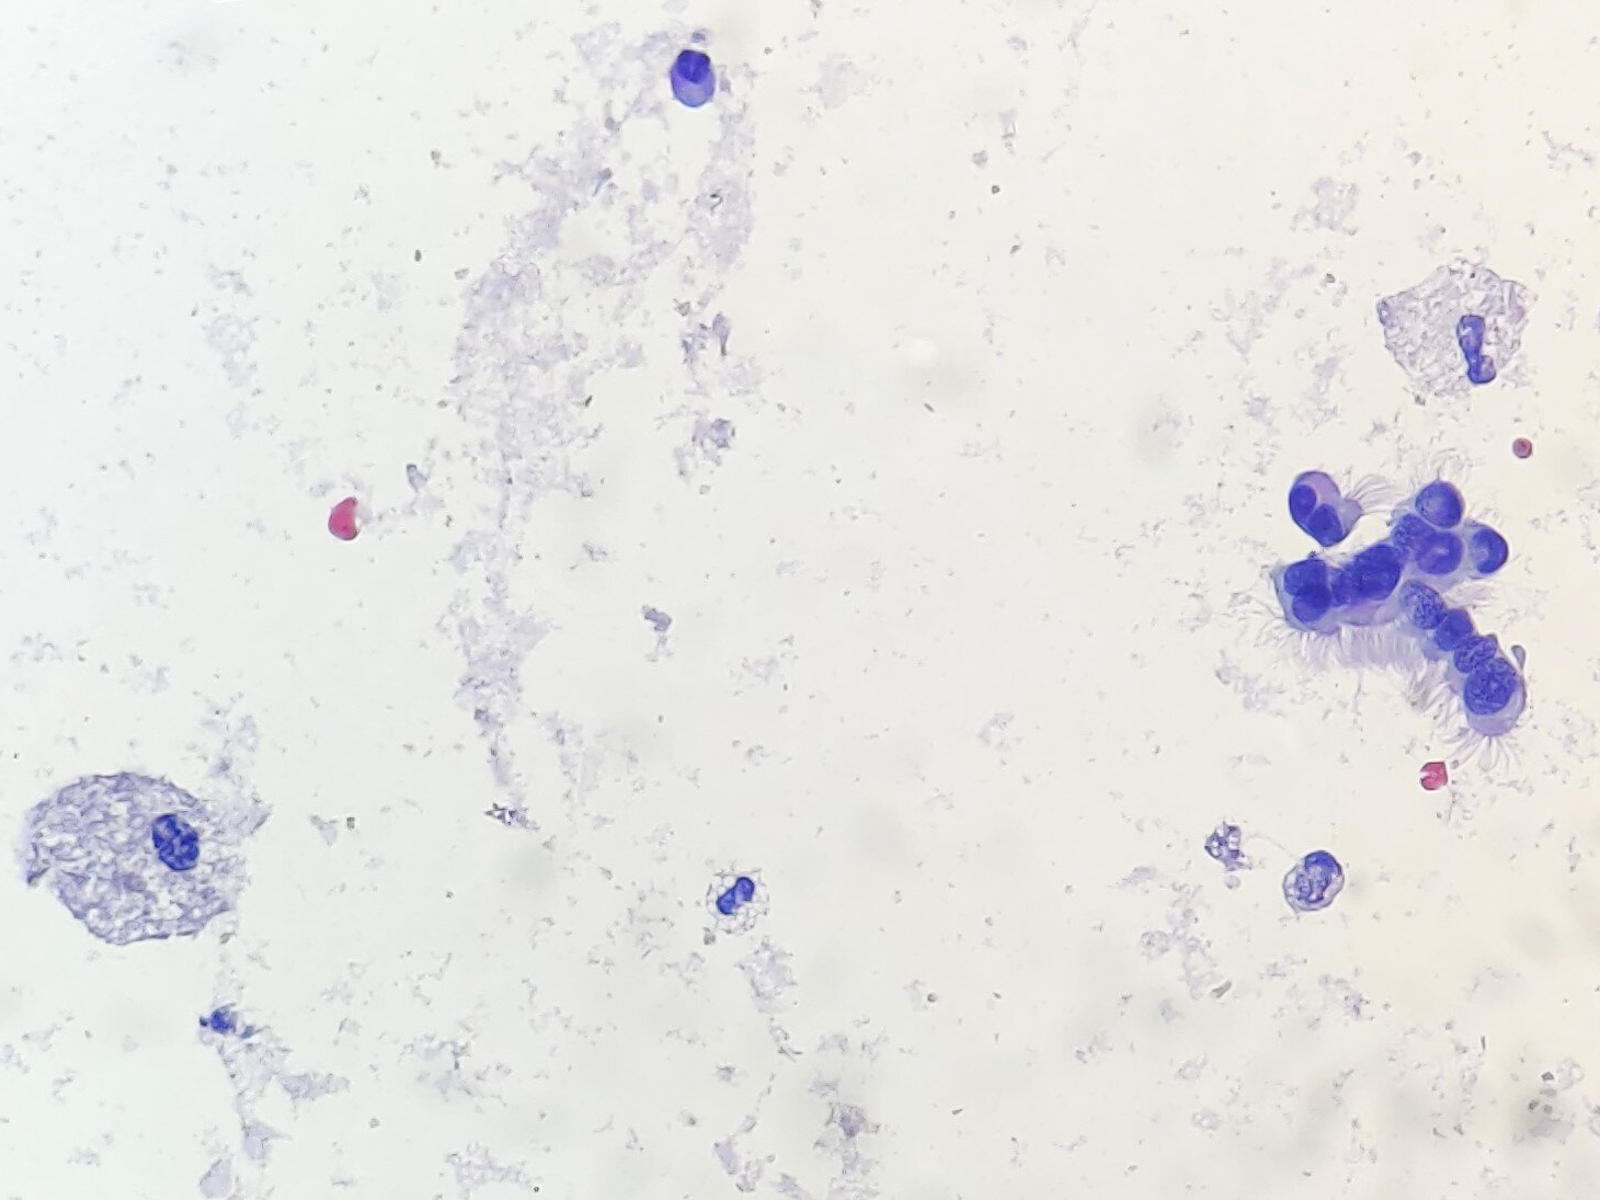

Cytology description

- Preoperative FNA is moderately sensitive but with many false negatives (Diagn Cytopathol 2005;33:365)

- FNA smears are of low cellularity, with predominant inflammatory cells outnumbering epithelial cells, similar to branchial cleft cyst:

- Macrophages, either foamy or hemosiderin laden

- Mature lymphocytes and neutrophils (predominantly if the cyst is infected)

- Squamous or ciliated columnar epithelium

- Colloid is common, ranging from thick and fragmented to thin and watery

- Admixture of cholesterol crystals

- Thyroid tissue found in < 10% of aspirates, likely due to deep embedding in the cyst wall

Cytology images

Contributed by Andrey Bychkov, M.D., Ph.D., Ayana Suzuki, C.T., Ram Kumar Kurpad R, M.B.B.S., M.D. and Y. C. Spoorthy Rekha, M.B.B.S., M.D.

Images hosted on other servers: